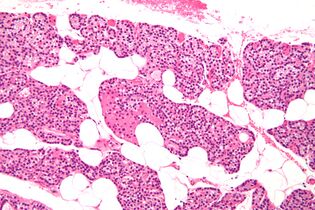

Microanatomy

The parathyroid glands are named for their proximity to the thyroid—and serve a completely different role than the thyroid gland. The parathyroid glands are quite easily recognizable from the thyroid as they have densely packed cells, in contrast with the follicular structure of the thyroid.[6] Two unique types of cells are present in the parathyroid gland:

- Chief cells, which synthesize and release parathyroid hormone. These cells are small, and appear dark when loaded with parathyroid hormone, and clear when the hormone has been secreted, or in their resting state.[7]

- Oxyphil cells, which are lighter in appearance and increase in number with age,[7] have an unknown function.[8]

Intermediate magnification micrograph. H&E stain. The white round structures are fat cells. Adipose tissue comprises 25–40% of normal parathyroid gland tissue.[7]